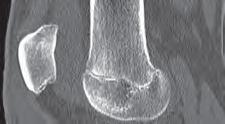

Podział złamań kości rosnących, tzw. złamań nasadowych: A – schematyczne przedstawienie klasyfikacji złamań; B – SH I (RTG, widok z przodu i z boku); C – SH II (RTG, widok z przodu i z boku); D – SH II (TK, widok z boku); E – SH III (RTG, widok z przodu i z boku); F – SH IV (RTG, widok z przodu i z boku); G – SH V (RTG, widok z przodu i z boku).

Rozpoznanie

Objawy złamania to silny ból uniemożliwiający stanie i chodzenie, zniekształcenie obrysów stawu kolanowego przez krwiak i różnego stopnia przemieszczenie nasady kości piszczelowej. Należy dokładnie zbadać stan ukrwienia i unaczynienia kończyny pod kątem objawów uszkodzenia tętnicy podkolanowej i nerwu strzałkowego. Trzeba ocenić bolesność uciskową oraz napięcie w przedziałach powięziowych podudzia: przednim, bocznym, tylnym powierzchownym i tylnym głębokim. U pacjentów z podejrzeniem wzmożonego ciśnienia wewnątrzprzedziałowego należy wielokrotnie powtarzać badanie ukrwienia i unerwienia kończyny, a w razie zaistnienia wskazań wykonać bezpośredni pomiar ciśnienia w przedziałach. Powinno się zawsze podejrzewać możliwość uszkodzeń więzadłowych współistniejących ze złamaniem. Badania obrazowe to RTG w pozycji AP, bocznej i skośnej. Wykonanie badania TK może być konieczne w celu pełnej oceny rozległości

złamania. W przypadku podejrzenia uszkodzenia tętnicy podkolanowej należy wykonać angio-TK lub arteriografię.

Leczenie złamania bliższej nasady piszczeli w przypadku uszkodzenia typu 1 i 2 według Saltera i Harrisa leczymy nieoperacyjnie. Należy wykonać zamkniętą repozycję i unieruchomić w opatrunku gipsowym udowym w zgięciu kolana 30–60°, zapewniającym najlepszą stabilność odłamów. Okres unieruchomienia wynosi od 6 do 7 tygodni. Po tym czasie usuwamy gips i zaczynamy ćwiczenia zwiększające zakres ruchomości stawu kolanowego oraz wzmacniające siłę mięśnia czworogłowego. Ważne jest, by prowadzić częste kontrole stanu ukrwienia i unaczynienia oraz kontrole radiologiczne w celu wykrycia ewentualnych przemieszczeń odłamów. Złamania pierwotnie niestabilne lub wtórnie przemieszczone wymagają zamkniętej repozycji stabilizacji drutami K. Typ 3 i 4

Złamania rzepki i podudzia

złamania według Saltera i Harrisa wymaga leczenia operacyjnego w postaci otwartej repozycji i stabilizacji śrubami. Należy unikać krzyżowania metalu zespalającego z chrząstką wzrostową. Kończynę zgiętą w kolanie do 30° unieruchamia się w gipsie udowym na okres 6–8 tygodni. Po tym czasie rozpoczynamy ćwiczenia czynne poprawiające zakres ruchomości kończyny.